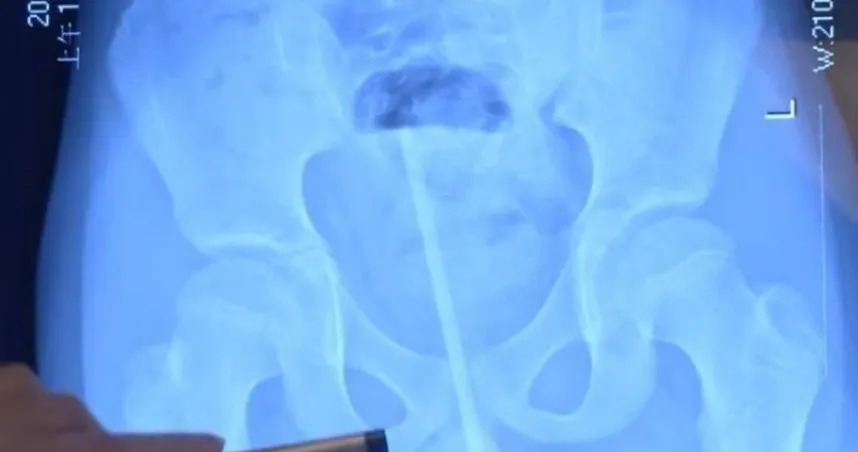

按摩

白內障

水晶體

福建省

眼睛

視力

視網膜

筋膜槍